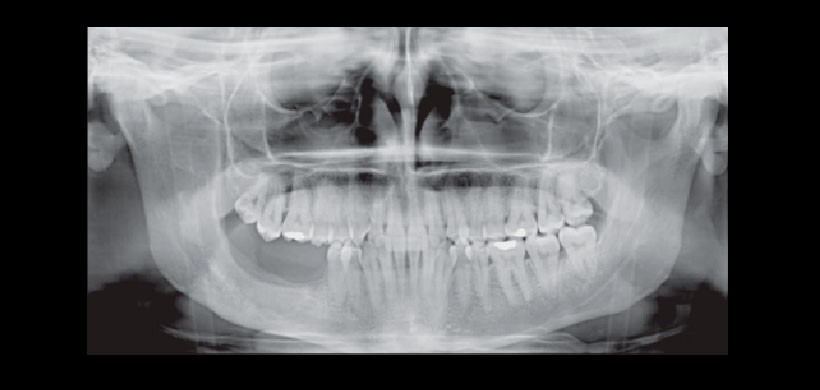

Figura 1: (A) Radiografía panorámica de un TOQ que se presenta como una gran radiolucidez multilocular con desplazamiento de piezas dentales y afección de maxilar inferior. Fuente: Srivatsan 2014. (B) Corte axial de un CBCT que muestra la extensión de la lesión producida por un TOQ. (Fuente: Alatorre 2014)

Figura 3: Imagen Inicial. OPG donde se observa la extensa lesión en rama y ángulo mandibular derecho